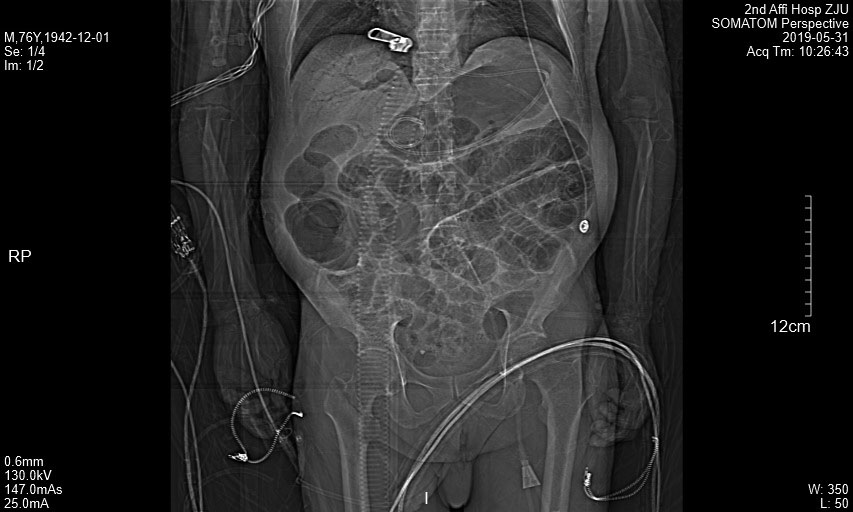

患者冠状面CT动图.gif

附图2  患者冠状面CT图